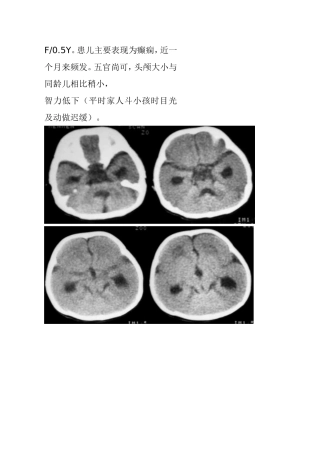

F/0.5Y。患儿主要表现为癫痫,近一个月来频发。五官尚可,头颅大小与同龄儿相比稍小,智力低下(平时家人斗小孩时目光及动做迟缓)。结果:...